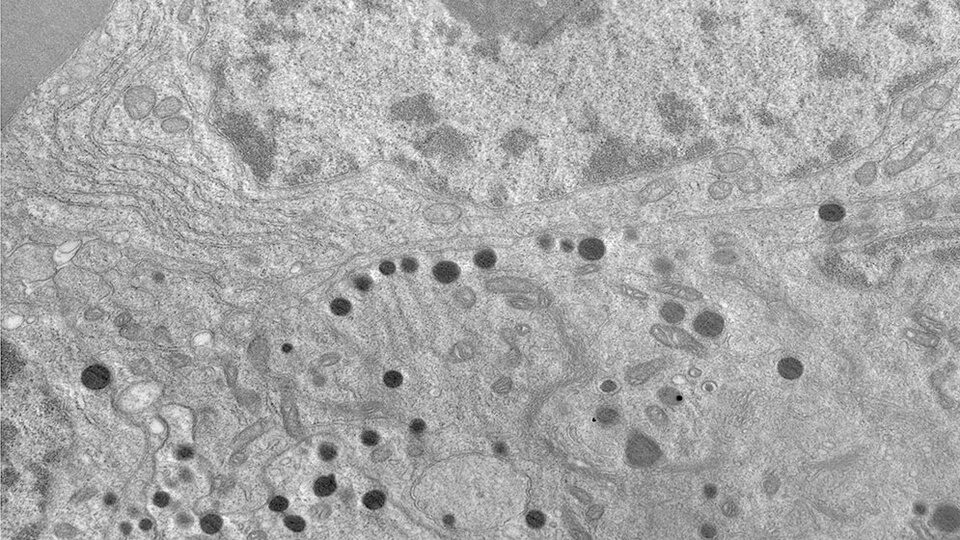

Células tumorales de pacientes con tumor somatotropo observadas mediante microscopio electrónico de transmisión. (Imagen: Conicet)

Los científicos argentinos identificaron una proteína llamada SHP2 que desempeña un papel clave en el crecimiento de ciertos tumores cerebrales, específicamente los tumores somatotropos de la hipófisis.

En tanto, el descubrimiento de que la inhibición de la proteína SHP2 puede reducir significativamente el crecimiento de estos tumores en modelos preclínicos sugiere una nueva vía terapéutica para aquellos pacientes que no obtienen resultados con las terapias convencionales.